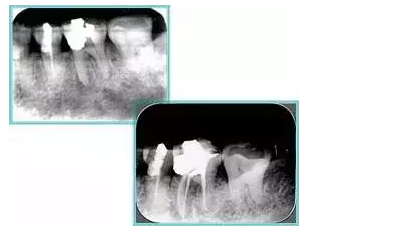

共有 4 張 X 線片,分別是術(shù)前、診斷絲 、主牙膠尖確認(rèn)、術(shù)后。

( 1 )術(shù)前:術(shù)前 X 線片用來了解牙齒的大概情況。術(shù)前預(yù)期為多根牙時 X 線片應(yīng)偏頭拍攝。

( 2 )診斷絲:根據(jù)術(shù)前 X 線片進(jìn)行開髓、根管的初步預(yù)備后,需要插入診斷絲,用來指示工作器械位置。常用 10 號或 15 號擴(kuò)大器作為診斷絲插入牙髓腔。

( 3 )主牙膠尖確認(rèn):通過術(shù)前預(yù)期和診斷絲診斷,明確工作長度、牙根走向,進(jìn)行根管預(yù)備。之后應(yīng)進(jìn)行主牙膠尖(中銼)確認(rèn),已明確根管是否適合充填。

( 4 )術(shù)后:觀察治療效果。